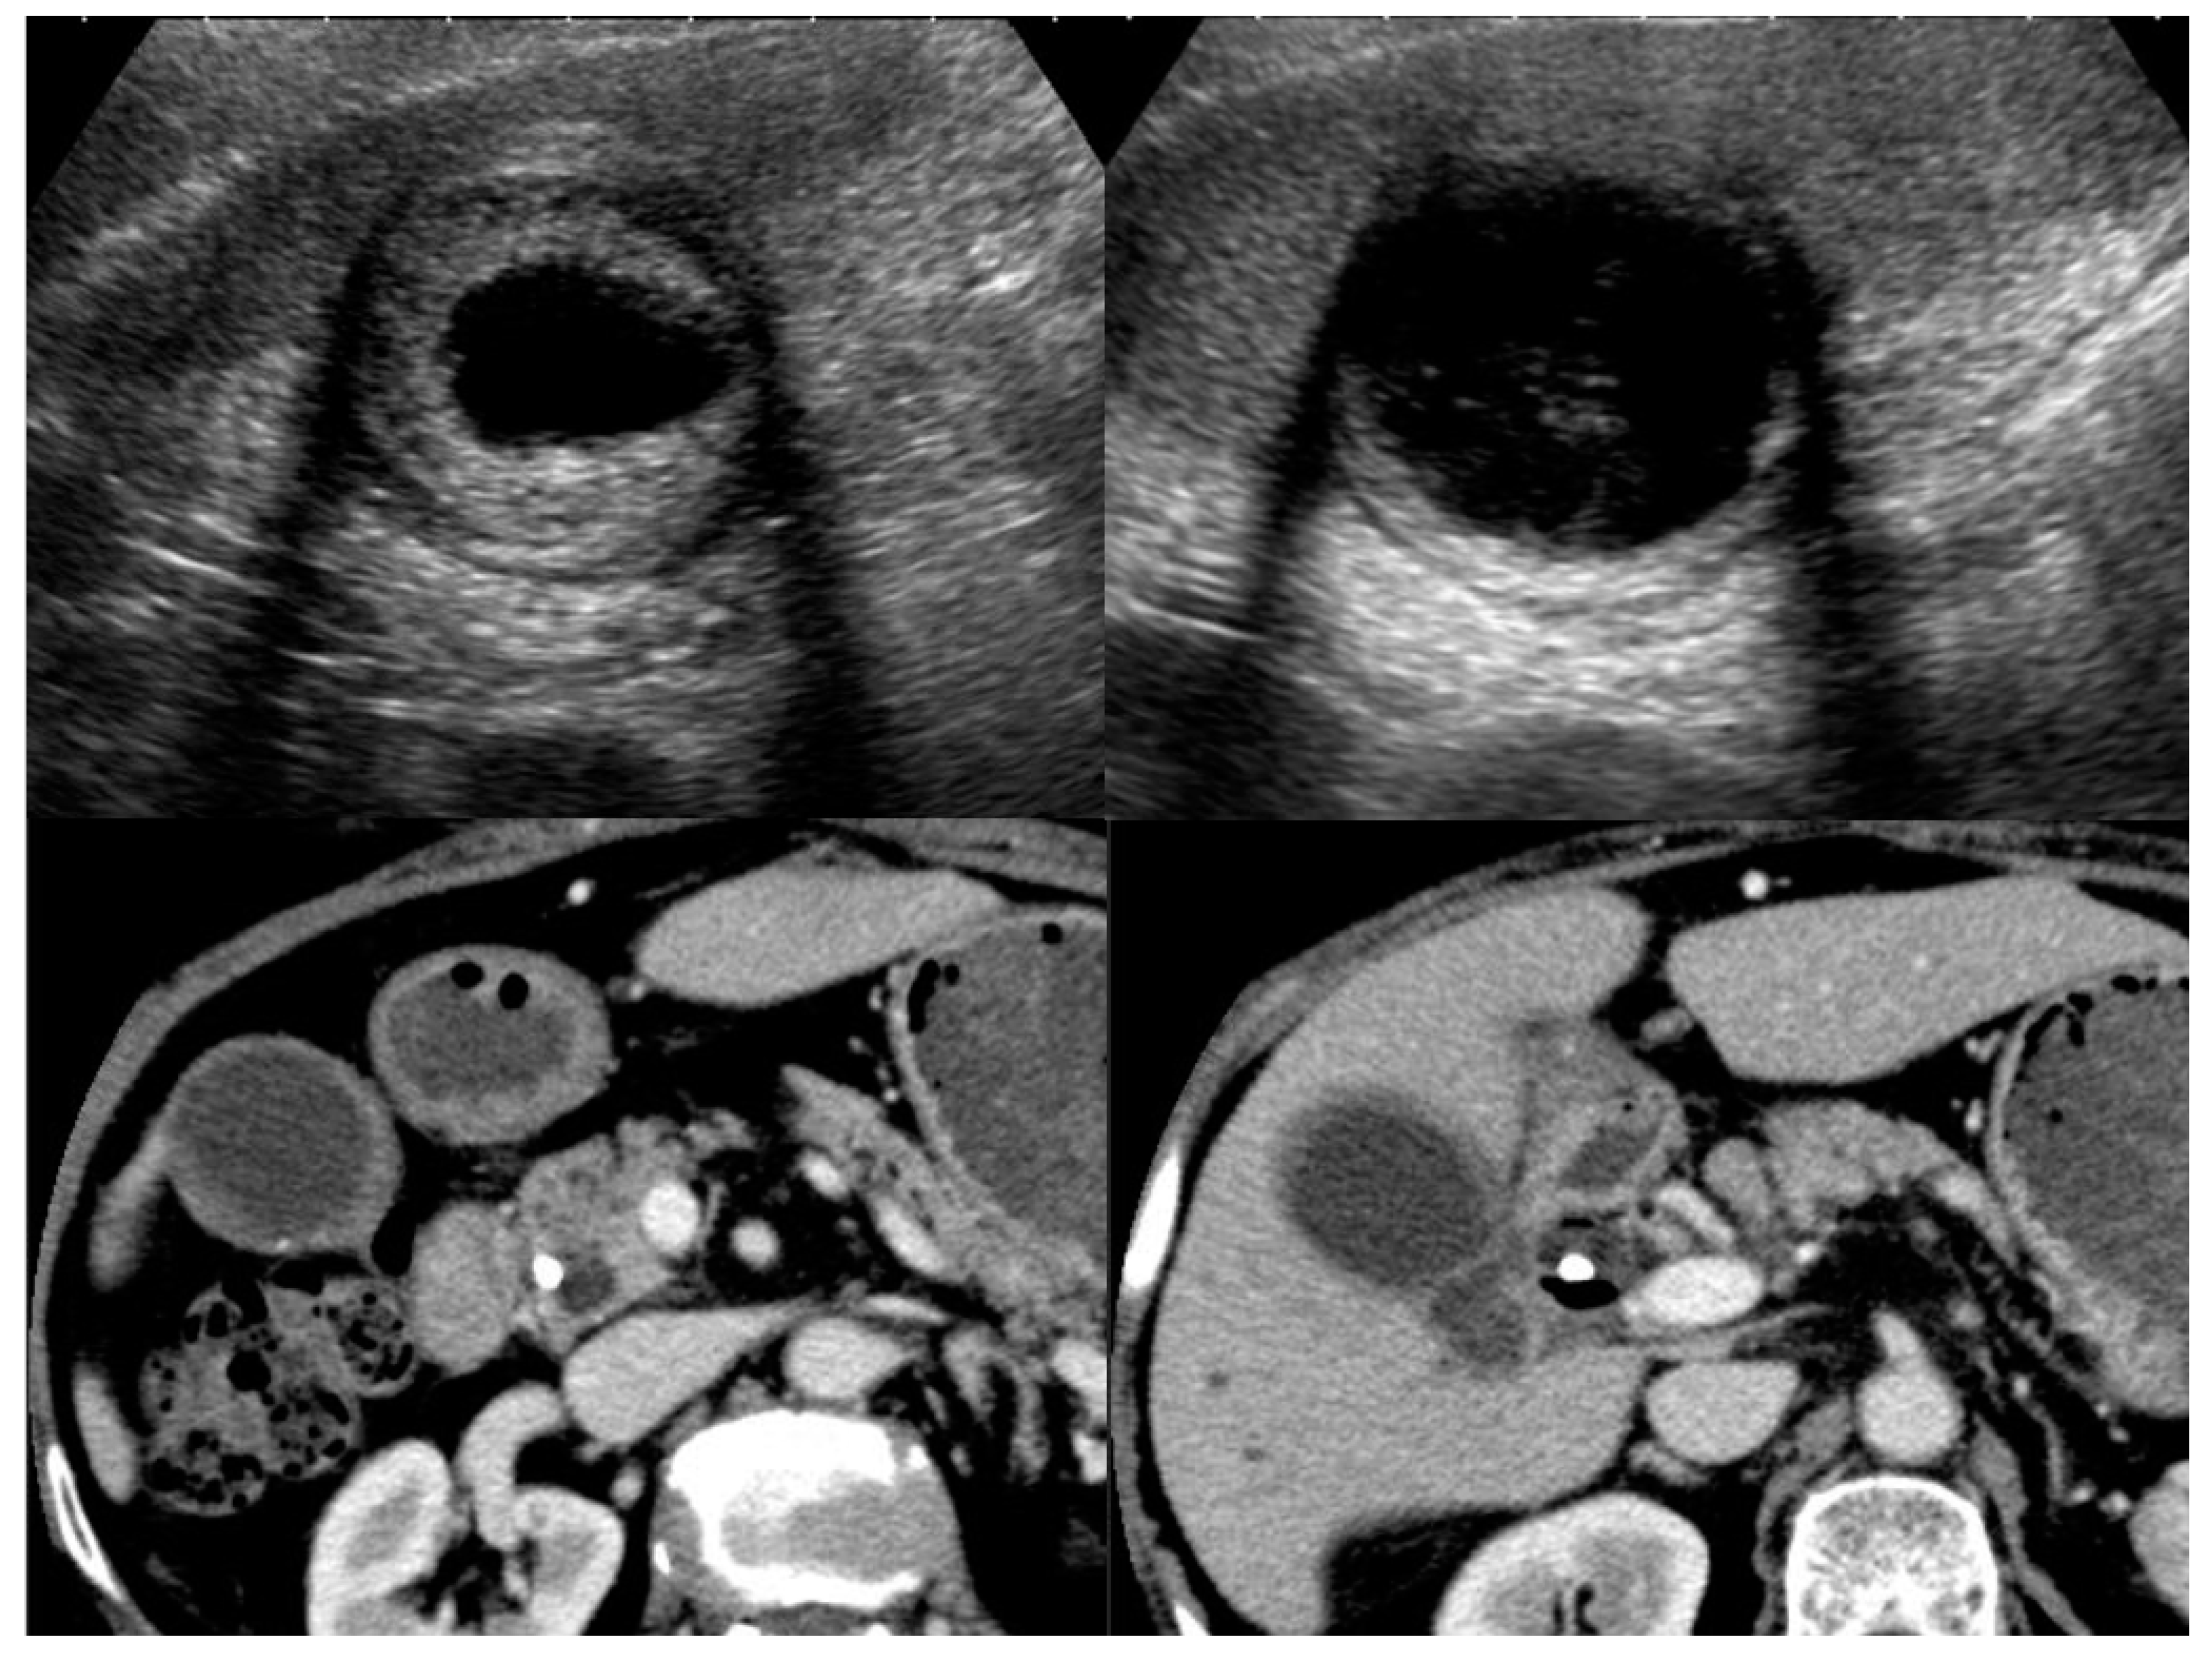

4. Image Features of IgG4-Related Sclerosing Cholecystitis

4.1. Diffuse Type of IgG4-CC

4.2. Localized Type of IgG4-CC